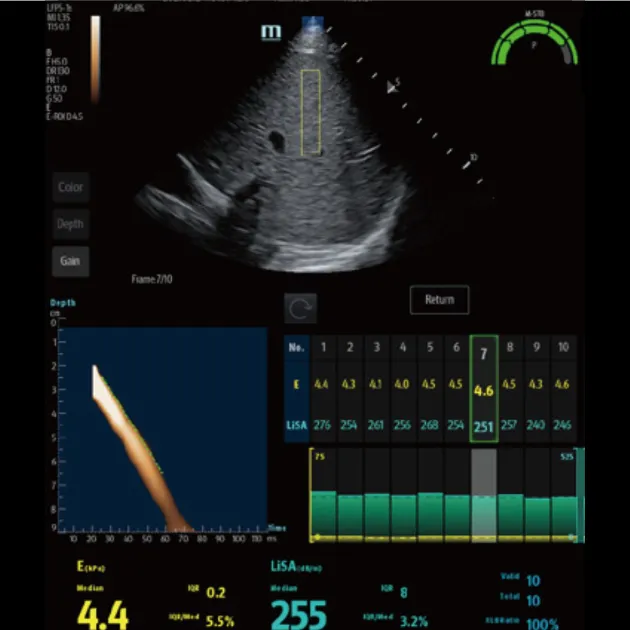

Количественный анализ ригидности печени Обеспечивает количественное определение жесткости печени и стадии фиброза печени с помощью технологии переходной эластографии

Количественный анализ стеатоза печени Количественная оцененка тяжести стеатоза печени с помощью технологии LiSA (поглощения ультразвука в печени).

Advanced ViTE (визуализированная транзиторная эластография)

- Проводить количественное выявление и оценку фиброза и стеатоза печени под визуальным контролем 2D-ультразвука в режиме реального времени

- Позволяет избежать образования кровеносных сосудов и повреждений, повысить точность и достоверность измерения

Быстрое интеллектуальное получение данных Q-сканирования

- Нажатием одной кнопки можно автоматически и непрерывно получать 10 групп эффективных данных и проводить интеллектуальный анализ

- Точные и достоверные результаты обнаружения могут быть получены немедленно, всего через 7 секунд после позиционирования

Надежный показатель контроля качества

- Индекс давления (P): качественный контроль давления зонда

- Индекс стабильности движения (m-STB): обеспечивает стабильность дыхания

- Четкая индикация с другим цветом для улучшения контроля качества во время обследования